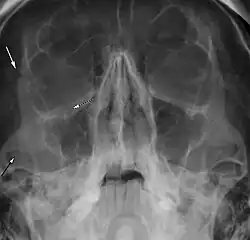

Right zygomaticomaxillary complex fracture with disruption of the lateral orbital wall, orbital floor, zygomatic arch and maxillary sinus.

The zygomaticomaxillary complex fracture, also known as a quadripod fracture, quadramalar fracture, and formerly referred to as a tripod fracture or trimalar fracture, has four components, three of which are directly related to connections between the zygoma and the face, and the fourth being the orbital floor. Its specific locations are the lateral orbital wall (at its superior junction with the zygomaticofrontal suture or its inferior junction with the zygomaticosphenoid suture at the sphenoid greater wing), separation of the maxilla and zygoma at the anterior maxilla (near the zygomaticomaxillary suture), the zygomatic arch, and the orbital floor near the infraorbital canal.